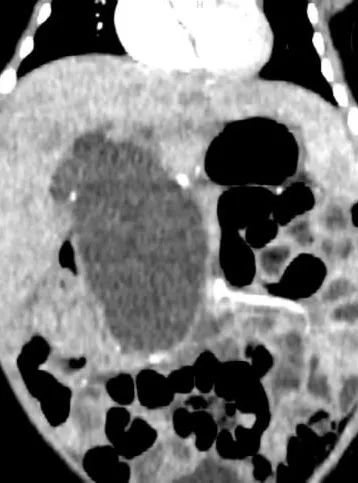

但计划赶不上变化。保守治疗3周后,宁宁的病情恶化——黄疸进行性加重,大便由黄色变成白色陶土样,胆红素迅速上升,胆总管囊肿的直径从4.5cm增长到6.8cm,这意味着出现了明显的胆道梗阻。

罗意革主任迅速组织多学科团队会诊,在多学科专家讨论后,认为宁宁病情进展迅速,胆总管囊肿破裂穿孔风险大,且短期内会引发肝功能衰竭。经过严谨的手术论证、影像学测绘和手术通道设计,和家属充分沟通后,团队决定为宁宁实施“单孔+1”机器人胆总管囊肿根治手术。